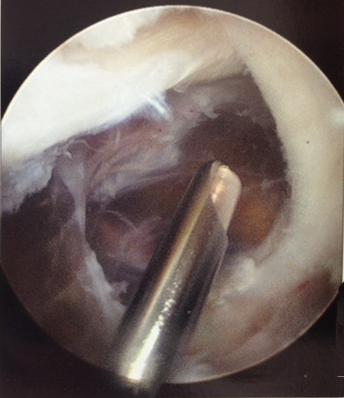

[Figure caption and citation for the preceding image starts]: Septae within a popliteal cystFrom the collection of Dr John D. Kelly IV; used with permission [Citation ends].